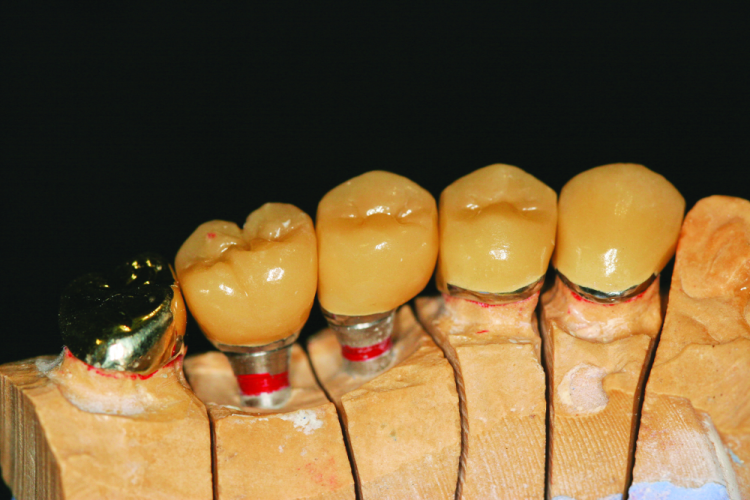

To assist the process, the mounting of a patient’s diagnostic casts remains an important step, as it allows the assessment of critical factors such as occlusion, implant position and forces direction.[2] It also allows exploration into prosthetic options,[2] such as angled abutments (Fig. 1).

Fig. 1: Implant treatment planning

Laboratory

If the clinician has delegated mounting to the laboratory, then the records phase has been completed. The following applies to those who mount their own casts. Position the tablet in the stand 6 to 12 inches from the cast and launch the VF app. Place the maxillary cast on the articulator mount (Fig. 9). The patient image will appear.

Adjust orientation of cast (tilt) to confirm alignment with the patient markers. Verify orientation of midline, incisal edges, occlusal plane and facial references (Fig. 10).

When the cast is correctly positioned, simply take a photo. Resize and reposition the image if required and save the image. Orientation can be confirmed by altering the transparency of either the face or cast image. Mount the maxillary cast to the upper articulator. The record of occlusal contacts (Fig. 8) will then be displayed. Position the mandibular cast to the maxillary cast, confirming contacts,and mount the mandibular cast.

The VF will then generate a composite of the skull, face and cast. The operator has the ability to alter the transparency of any image to reconfirm the position of the skull to the patient’s face and, ultimately, to the cast (Fig. 11). The laboratory component has been completed (Fig. 12).

The VF also records the maxillo-mandibular relationship vital to correct mounting, enabling the accurate mounting of complex implant cases (Fig. 13). With exact mounting, the proper position and angulation of dental implants can be achieved.